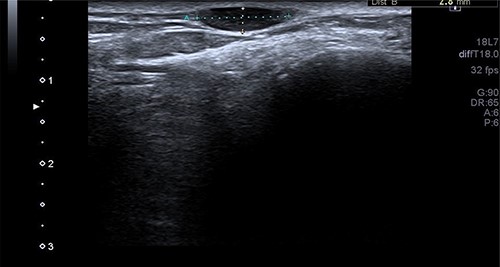

A 34-year-old gentleman presented with a swelling over the posterolateral aspect of his right ankle close to the Achilles tendon. He complained of pain and sensitivity to wearing shoes. The swelling was 10 × 5 mm, mobile and ultrasound (US) scan reported it as ‘A well-defined ovoid hypoechoic lesion underneath the skin surface measuring approximately 11 mm × 3 mm in diameter and appears related to a linear hypoechoic structure’ (Fig. 1). ‘The lesion is slightly heterogeneous in texture and shows posterior acoustic enhancement on the underlying tissues. There is mild internal vascularity of this lesion on Doppler assessment’ (Fig. 2) and ‘these appearances are suggestive of superficial neuroma lesion’. Post-excision, the histology of a single piece of pale smooth firm tissue (9 × 6 × 5 mm) was reported as angioleiomyoma. He made an uneventful recovery and was discharged after 4 months of follow-up.

The Doppler US image of the right ankle posterolateral aspect of Patient 1, which shows mild internal vascularity.

An arteriogram or Doppler study may be useful to an extent, but a confirmed diagnosis is only obtained through histopathological examination after excision [8–10]. Case 1 had an US scan of the swelling which showed a well-defined ovoid hypoechoic lesion underneath the skin surface, and the lesion was slightly heterogeneous in texture and shows posterior acoustic enhancement on the underlying tissues. There was mild internal vascularity of this lesion on Doppler assessment—appearances suggestive of superficial neuroma lesion. The usual appearance of these lesions on USS is a well-circumscribed oval mass with a homogenous echotexture and occasionally hypoechoic protrusions.